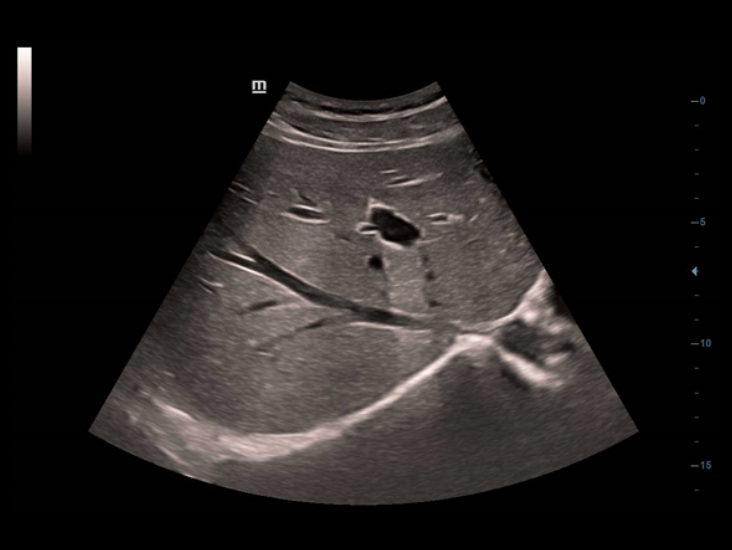

Teknologi pencitraan klasik: meningkatkan mutu diagnosis

Dengan penerapan teknologi pencitraan klasik, yang dimigrasikan dari sistem ultrasound yang sudah terbukti, DC-40 dengan Full HD memberikan peningkatan mutu akan detail gambar.

- iClear (teknologi pencitraan reduksi speckle)

- PSH (Pencitraan Phase Shift Harmonic)

- iBeam: Teknologi spatial-compounding imaging